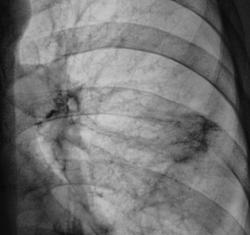

Сегодня, после проведения противовоспалительной (неспецифической) терапии пациент дан на контроль.

Прямая проекция.

Такое ощущение, что тень стала меньше? Может аутоиммуной природы процесс?

но ведь патология есть! тень была больше, стала чуть меньше! динамика есть! осталось определить, что это?

Осталось определиться, что мы видели первично. Что это "процесс", или "парапроцесс" вокруг "другой нозологии".